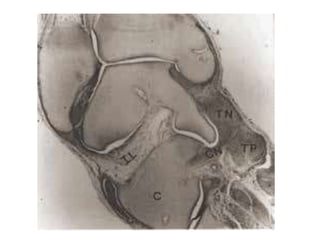

• Talus: most deformed and least displaced.

Head & neck deviated medially & plantarward

Body rotated externally in the ankle mortise,

superior articular surface escapes from mortice.

Talar neck is short and medially deviated.

Smaller than normal, disturbance of vascular

supply, ossification centre eccentrically placed.

• Navicular:

Medially displaced

Close to medial malleolus

Articulates with medial surface of head of talus

• calcaneus is

– adducted and

– inverted under the talus

• Cuboid

Displaced medially on the dysmorphic distal end

of the calcaneus